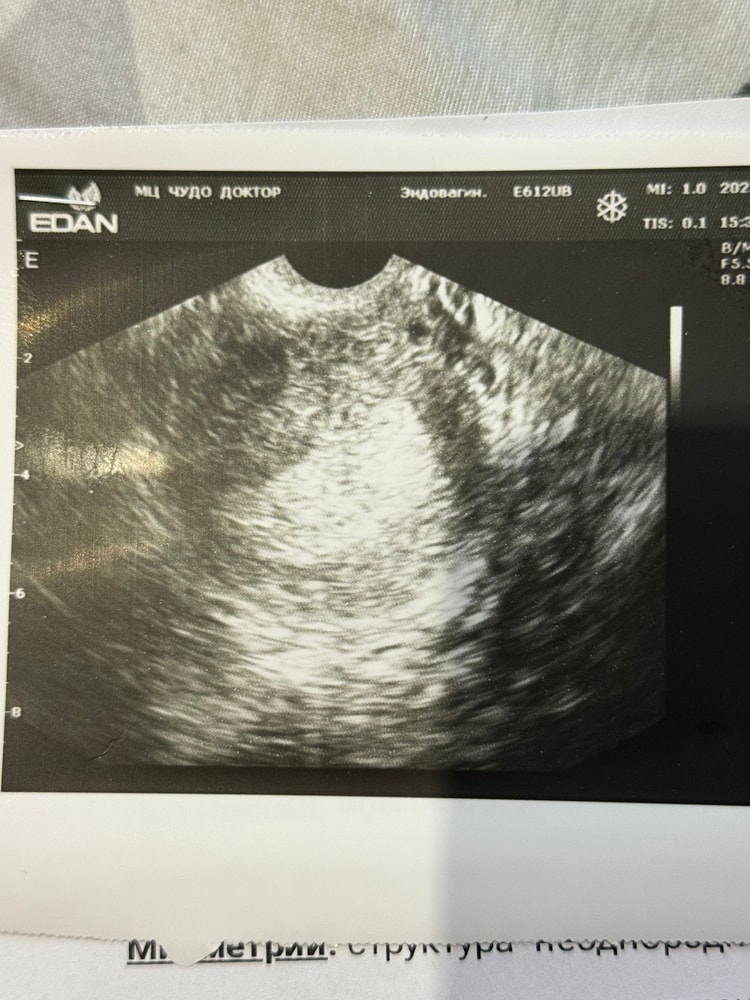

Изображение

По фото матка пустая, ищите у другого специалиста